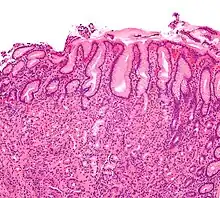

Micrograph showing gastritis. H&E stain.